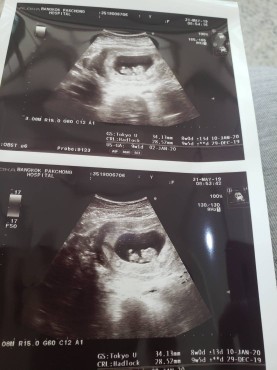

8w พอดีค่ะภาพแรก ตอนนี้ 10wค่ะ

ตอน 8 วีคค่ะ ตอนนี้ 33 วีค 5 วันค่ะ

ท้องแรก ตอนนี้14วีคแล้วค่ะ 💜

4ปีที่รอคอยค่ะ รู้ตัวก็10wแล้ว

ภาพแรกของหนู ตอนอายุครรภ์ 7W6D

ซาวตอน8weekตอนนี้36weekแล้วจ้า

ภาพแรกตอน 10 week จ้า ตอนนี้ 25 week

ตอน5วีค คะ ตอนนี้ 17+3เเล้วคะ

ตอน12วีคคะ ตอนนี้20วีคแล้ว

ภาพแรกตอน 3 เดือนค่ะ